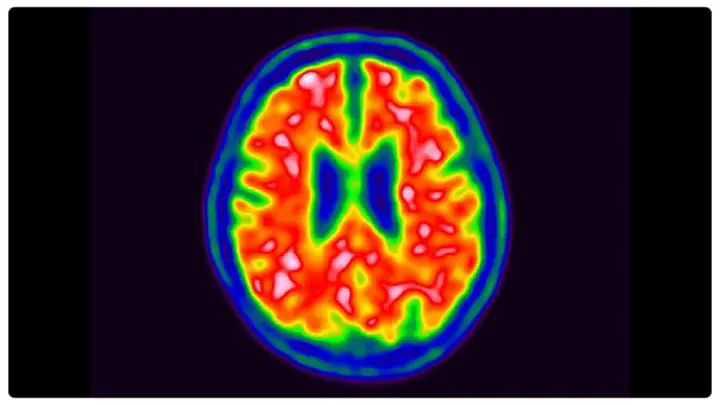

Traditional diagnostic techniques such as cerebrospinal fluid (CSF) neurochemical tests and amyloid-PET imaging are effective but not suitable for widespread screening because they are invasive, costly, and logistically challenging. This has led to the development of blood-based biomarkers, which could revolutionize early AD detection and help in patient selection for preventive treatments.